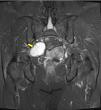

MethodsWe conducted a retrospective analysis of 19 cases of patients with neurogenic tumors in the sacral area who were diagnosed and underwent surgery at our center. Of them, 8 were male and 11 were female. They had a mean age at diagnosis of 51 years (with an age range of 25–78 years). Six patients were asymptomatic and were diagnosed incidentally, while the majority (11 patients) presented with lumbar pain accompanied by other symptoms: pain radiating to the legs, pelvic pain, sensory alterations and loss of strength in the legs. Two patients presented with another primary symptom on diagnosis: pain in the pelvic region and in the left leg. All patients underwent a least one imaging test (MRI/CT scan). Nine patients had tumors limited to the sacrum or with subsequent spread, with surgery via the posterior route. In 6 cases, an exclusively anterior approach was employed owing to the pre-sacral location of the tumor; 4 cases required both an anterior and posterior approach.

ResultsThe 6 patients who were asymptomatic at diagnosis continued to have no symptoms after surgery. In 8 patients, symptoms resolved after surgery, and at discharge 4 had pain in the lumbar region or legs, which improved in subsequent consultations. One patient had symptoms consistent with motor and sensory deficit in the right leg deriving from impairment of the external popliteal sciatic nerve. The mean follow-up period was 69 months (6–178 months). Histologically, 17 cases were classified as schwannomas, one case was classified as neurofibroma, and one case was classified as neurofibrosarcoma, which received radiotherapy. Three patients with benign histologies had further surgery for local recurrences.